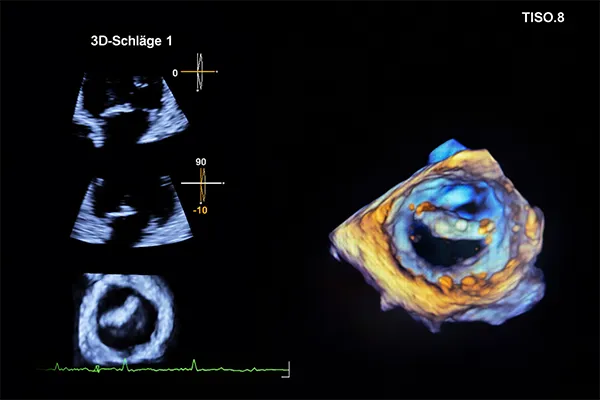

Diagnostische Verfahren in unserer Klappstunden

Erweiterte Diagnostik und weitere Verfahren der ambulanten Klappensprechstunde

Je nach individueller Fragestellung stehen uns weitere diagnostische Verfahren zur Verfügung:

- Stressechokardiographie: Ultraschall des Herzens unter Belastung zur Beurteilung des Schweregrades eines Klappenfehlers